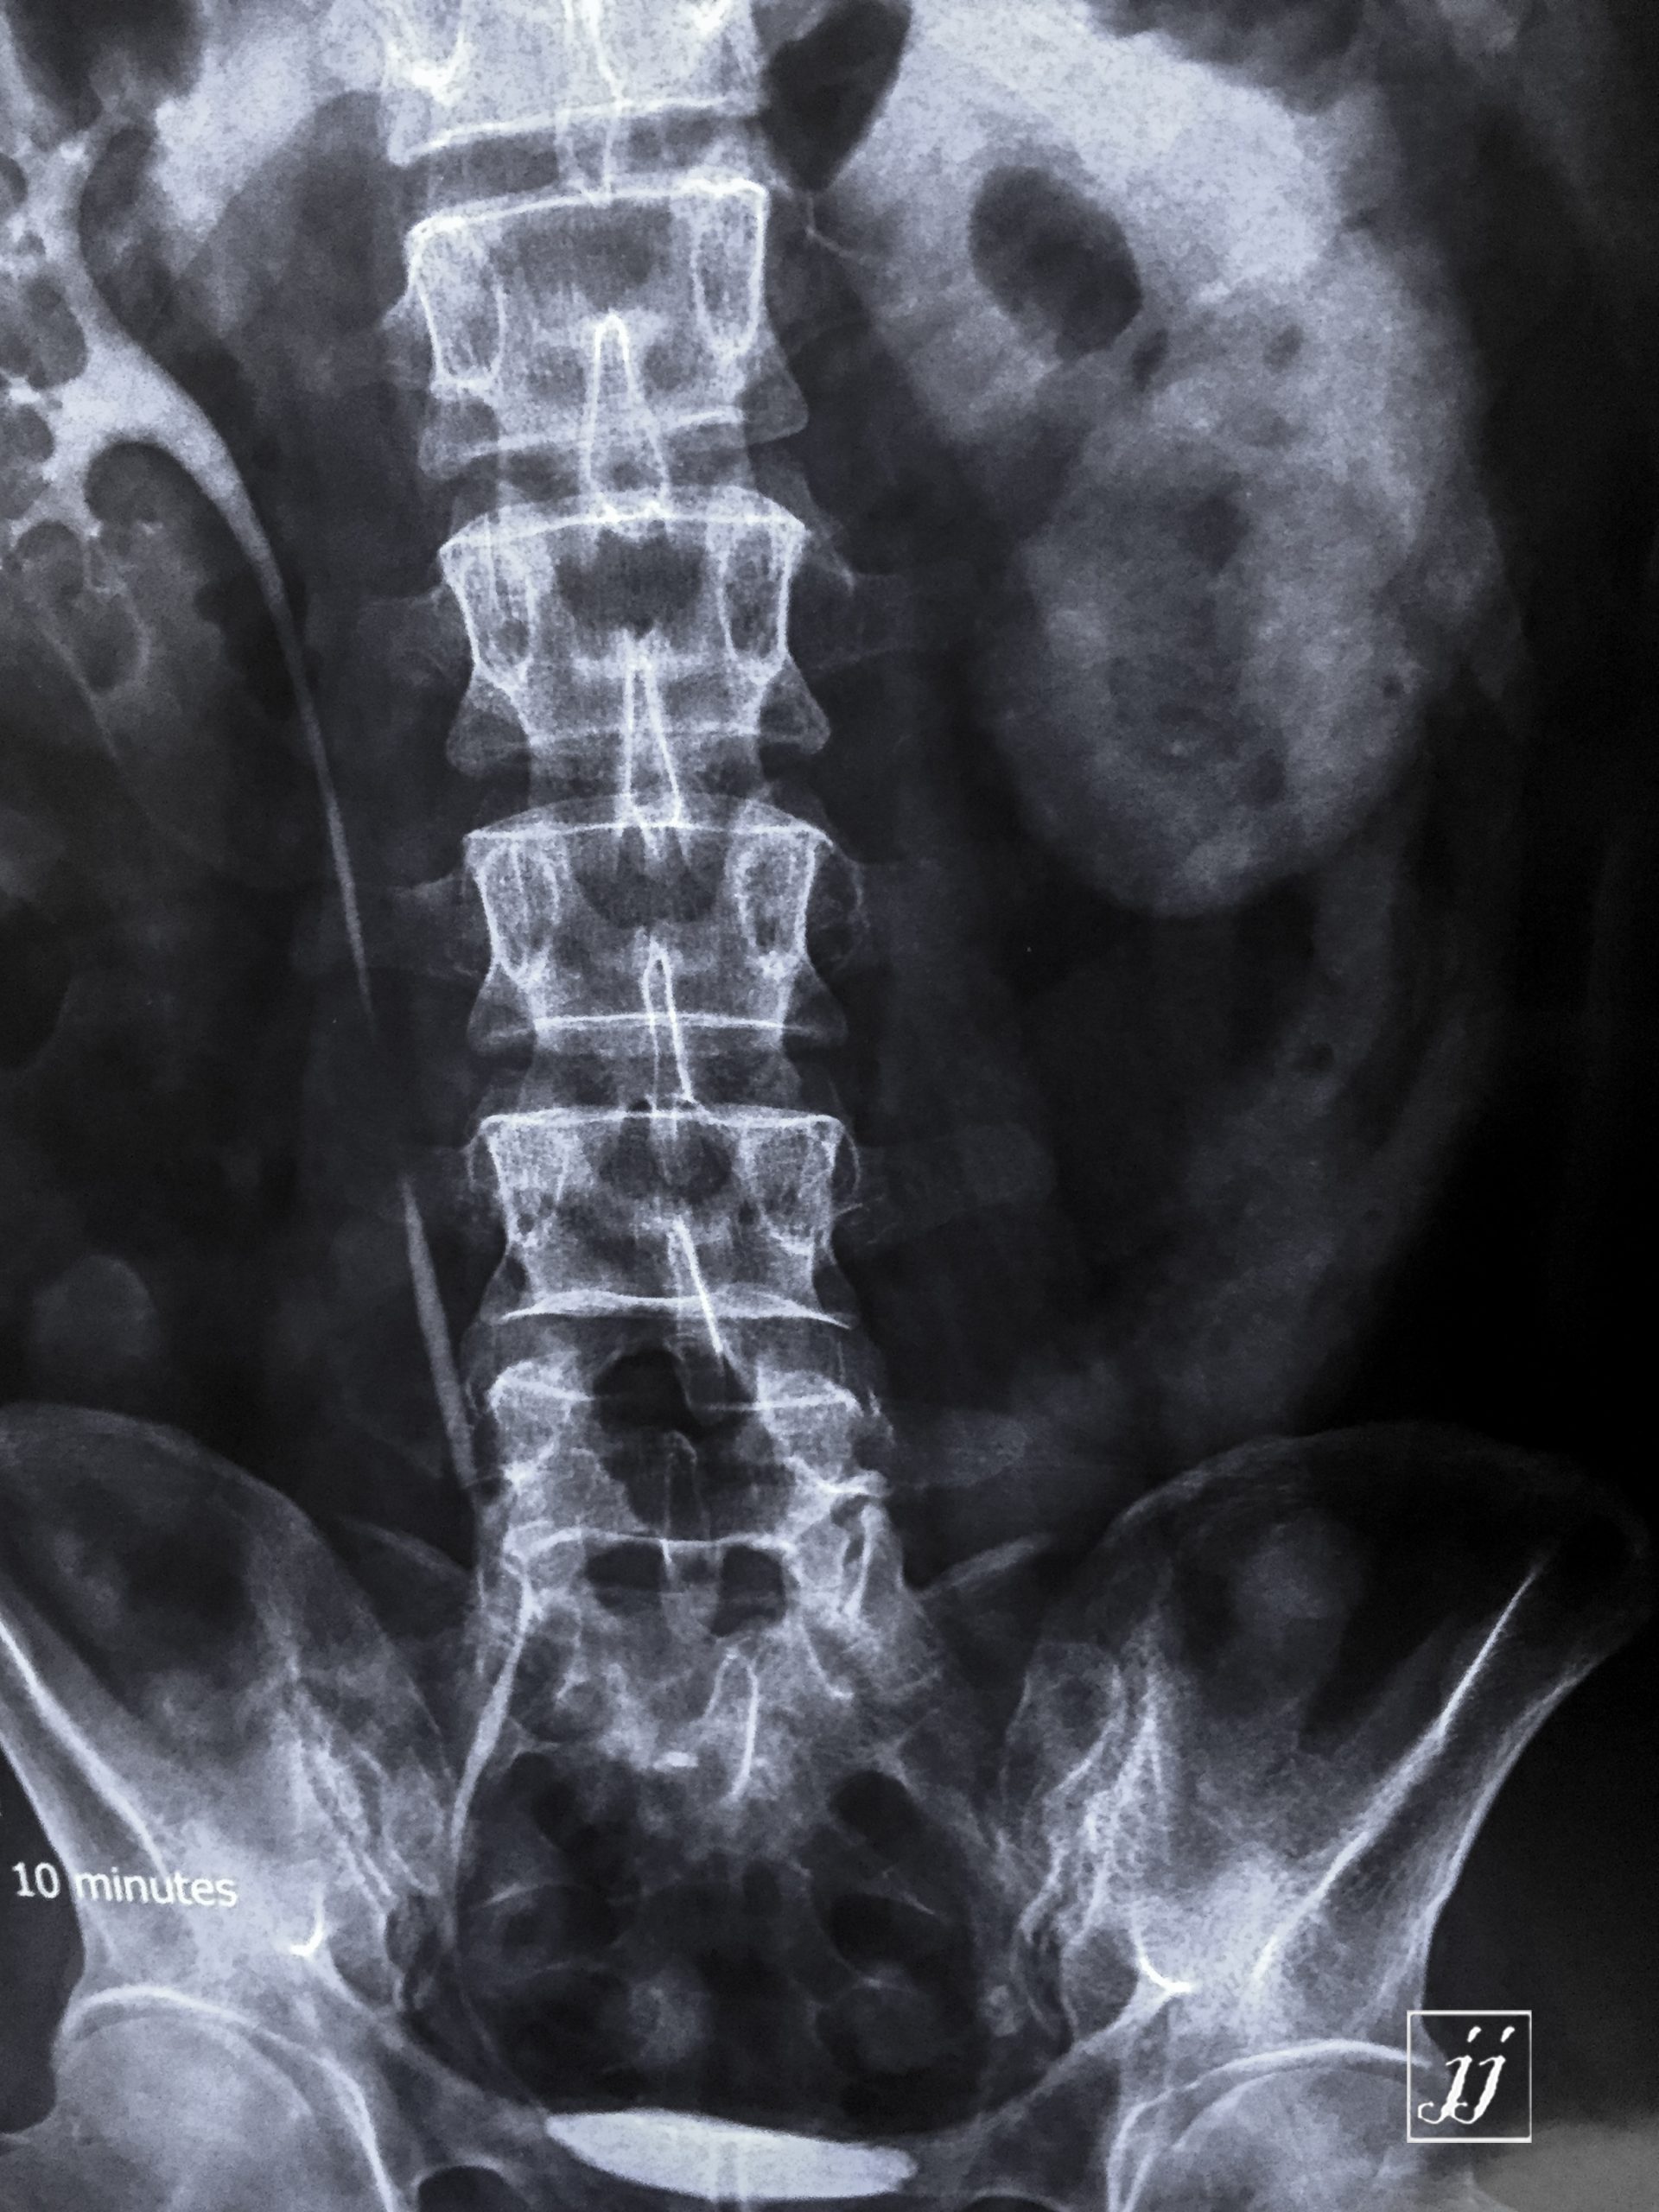

Abdomen- left lower ureter stone and delay of left kidney (4)